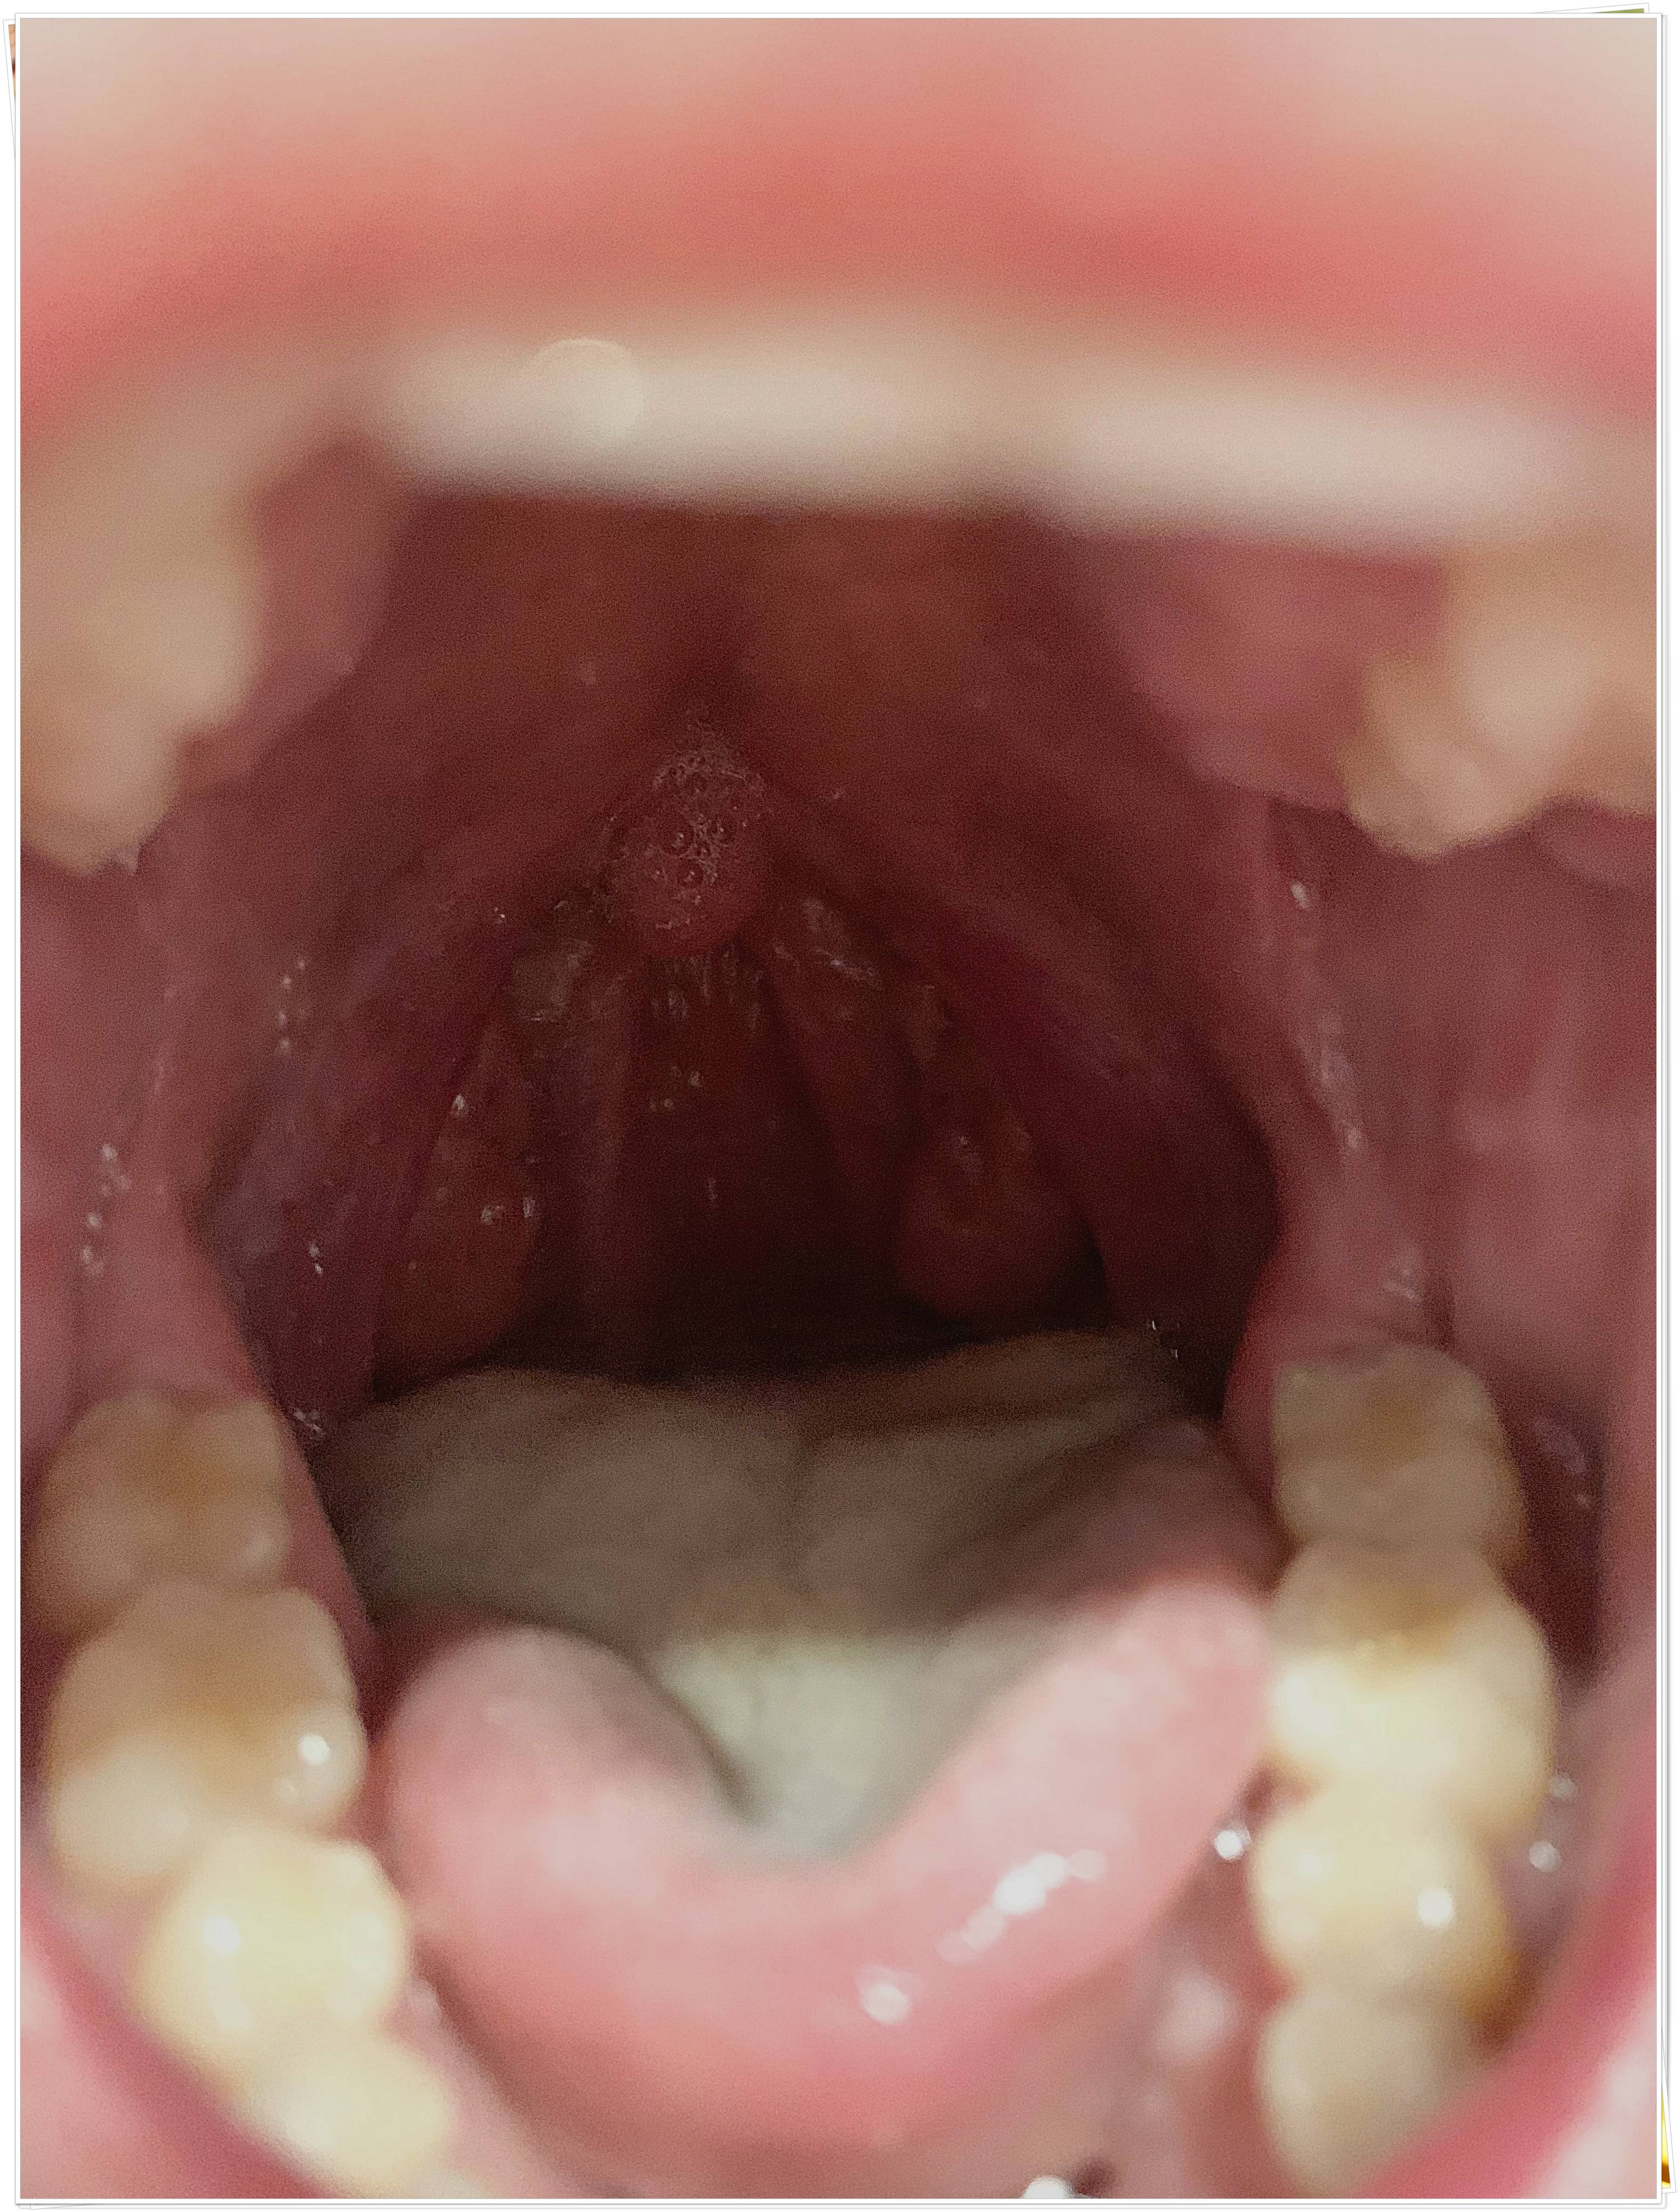

- 편도 부위의 흰색·노란색 알갱이

- 거울로 목 안쪽을 비춰봤을 때 작은 결석이 보인다.